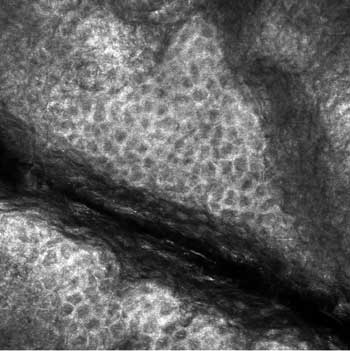

Mit der konfokalen Laserscanmikroskopie stehe eine nicht invasive In-vivo-Technologie zur Verfügung, die horizontale Schnitte der Haut mit guter zellulärer und subzellulärer Auflösung zeige (Abbildung). Das Verfahren biete die Möglichkeit, Epidermis und Dermis schichtweise von der Hornschicht bis zur oberen Dermis zu erfassen und bis zu einer Eindringtiefe von etwa 300 Mikrometer zelluläre Unregelmäßigkeiten zu evaluieren.

| Konfokales Bild (500 x 500µm) des Stratum granulosum von normaler, unbehandelter Haut (In-vivo-Aufnahme mit 445nm-Laser). Die Zellkerne im Zentrum der Zelle sind als dunkle Areale dargestellt, während der zytoplasmatische Rand hell und körnig erscheint. |